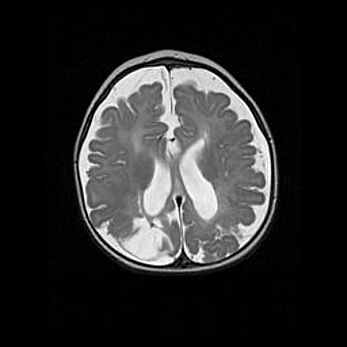

Лейкомаляция с кистозно-глиозной дегенерацией головного мозга.

Возраст: 2 месяца 25 дней

Вес: 6400 г

Окружность головы: 40 см

Срок гестации: 41 неделя

Лейкомаляцию относят к ишемически-гипоксическим повреждениям головного мозга, диагностируемым у новорожденных. При лейкомаляции в головном мозге обнаруживают очаги некроза, возникшие после тяжелой гипоксии и нарушения кровотока. В процессе морфогенеза очаги проходят три стадии: 1) развития некроза, 2) резорбции и 3) формирования глиозного рубца или кисты. Перивентрикулярная лейкомаляция (ПЛ) встречается примерно в 12% случаев среди новорожденных, обычно – у недоношенных детей, причем, частота ее зависит от массы, с которой младенец появился на свет. Наибольшее число малышей страдает лейкомаляцией, если масса при рождении 1500-2500 г.